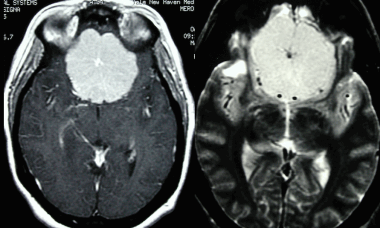

МРТ при менингиомах

МРТ с использованием гадолиния является наилучшим способом визуальной оценки менингиом. Важными преимуществами МРТ в диагностике менингиом являются хорошая визуализация разных типов мягкой ткани, возможность получения изображений в разных плоскостях, а также реконструкции объемного (3 D ) изображения.

МРТ также хорошо демонстрирует васкуляризацию опухоли, прорастание артерий и инвазию опухоли в венозные синусы, а также взаимное расположение опухоли и подлежащих структур. Особенно полезной МРТ с гадолинием оказывается для отображения структур параселлярного пространства, задней черепной ямки, и, в редких случаях, опухолевых отсевов по путям оттока спинномозговой жидкости. Возможность получения изображений в разных плоскостях позволяет наилучшим образом визуализировать зону контакта менингиомы с мозговыми оболочками, капсулу опухоли, а также выявить особенности контрастирования мозговых оболочек в участках, непосредственно прилежащих к опухоли.

На Т2-взвешенных изображениях, полученных без контрастного усиления, интенсивность сигнала в большинстве случаев не отличается от таковой серого вещества коры. Фиброматозные менингиомы могут иметь более гипоинтенсивный сигнал по сравнению с корой головного мозга. Т1-взвешенные изображения могут использоваться для оценки наличия некроза и кист, а также следов кровоизлияний в опухоль. На Т2-взвешенных изображениях интенсивность сигнала варьируется. Т2-взвешенные изображения тоже могут быть использованы для обнаружения последствий кровоизлияний в опухоль и визуализации кистозных образований. Кроме этого, Т2-взвешенная ИП используется для определения наличия кармана между опухолью и паренхимой головного мозга с затеканием СМЖ, что свидетельствует об экстрааксиальном расположении образования.

Гиперинтенсивность сигнала на Т2-взвешенных изображениях указывает на мягкотканую структуру опухоли и ее обильную капиллярную васкуляризацию. Это более характерно для агрессивных ангиобластных или менинготелиальных опухолей. Интенсивность сигнала на Т2-взвешенных изображениях хорошо коррелирует как с гистологическим строением, так и с консистенцией менингиомы. В целом, участки пониженной интенсивности в опухоли соответствуют более плотной, фиброзной, структуре образования (например, в случае фибробластных менингиом), в то время как гиперинтенсивные участки указывают на более мягкотканую структуру опухоли (например, в случае ангиобластной менингиомы).

Последовательность FLAIR (режим инверсия-восстановление с подавлением сигнала от воды) удобно использовать для визуализации сопутствующего отека, а также т.н. «дурального хвоста». Дуральный хвост представляет собой линейный участок контрастного усиления, соответствующей непосредственно прилежащей к опухоли твердой мозговой оболочке. Дуральный хвост наблюдается примерно в 65%, а также в 15% случаев при других опухолях. Несмотря на то, что данный признак не является специфичным, при его наличии такой диагноз становится одним из наиболее вероятных.

Как при МРТ, так и при КТ одинаково отвечают на введение контрастного вещества. Интенсивное контрастирование гадолинием наблюдается в более 85% случаев. Кольцевое распределение контраста может соответствовать капсуле образования. Использование гадолиния также улучшает визуализацию плоских менингиом типа en plaque , которые могут быть не видны на изображениях без контрастного усиления.

Парасагиттальная менингиома на МРТ с контрастным усилением. Видно гомогенное округлое образование, активно накапливающее контрастное вещество.

Менингиома височной области. На серии последовательных МР-изображений видно крупное образование правой височной области с паттерном контрастирования по типу «колеса со спицами», местным объемным воздействием, отеком окружающих тканей и гиперостозом подлежащей кости.

Менингиома теменной области. МР-изображения, полученные с использованием следующих последовательностей: аксиальное Т2-взвешенное, аксиальное Т2-взвешенное, корональное FLAIR -изображение и сагиттальное Т1-изображение. Крупная левосторонняя менингиома выглядит в виде экстрааксиального образования с паттерном «колеса со спицами» и отеком окружающих тканей.